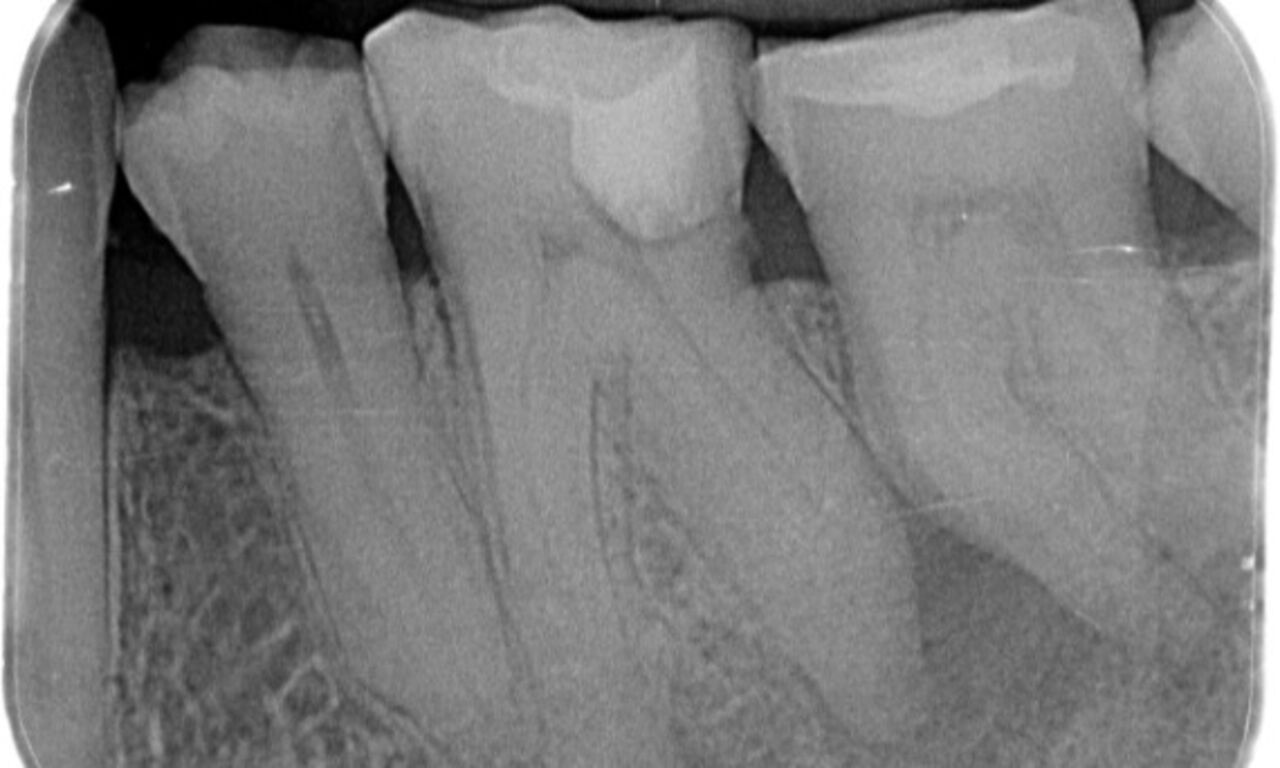

Upon examination, there was a caries lesion related to the lower right first molar. Radiographic examination revealed proximity of the lesion to the pulp horn and combining it with the chief complaint, a final diagnosis of chronic irreversible pulpitis was concluded.

Access cavity was done as conservative as possible. TruNatomy was the system of choice due to the young patient’s age. We needed to preserve dentine as much as possible to increase the tooth ability to overcome occlusal load and increase the longevity of the final restoration.

"I chose TruNatomy to be able to preserve as much dentin as possible to overcome occlusal load and increase the longevity of the tooth."

Dr. Abuelezz